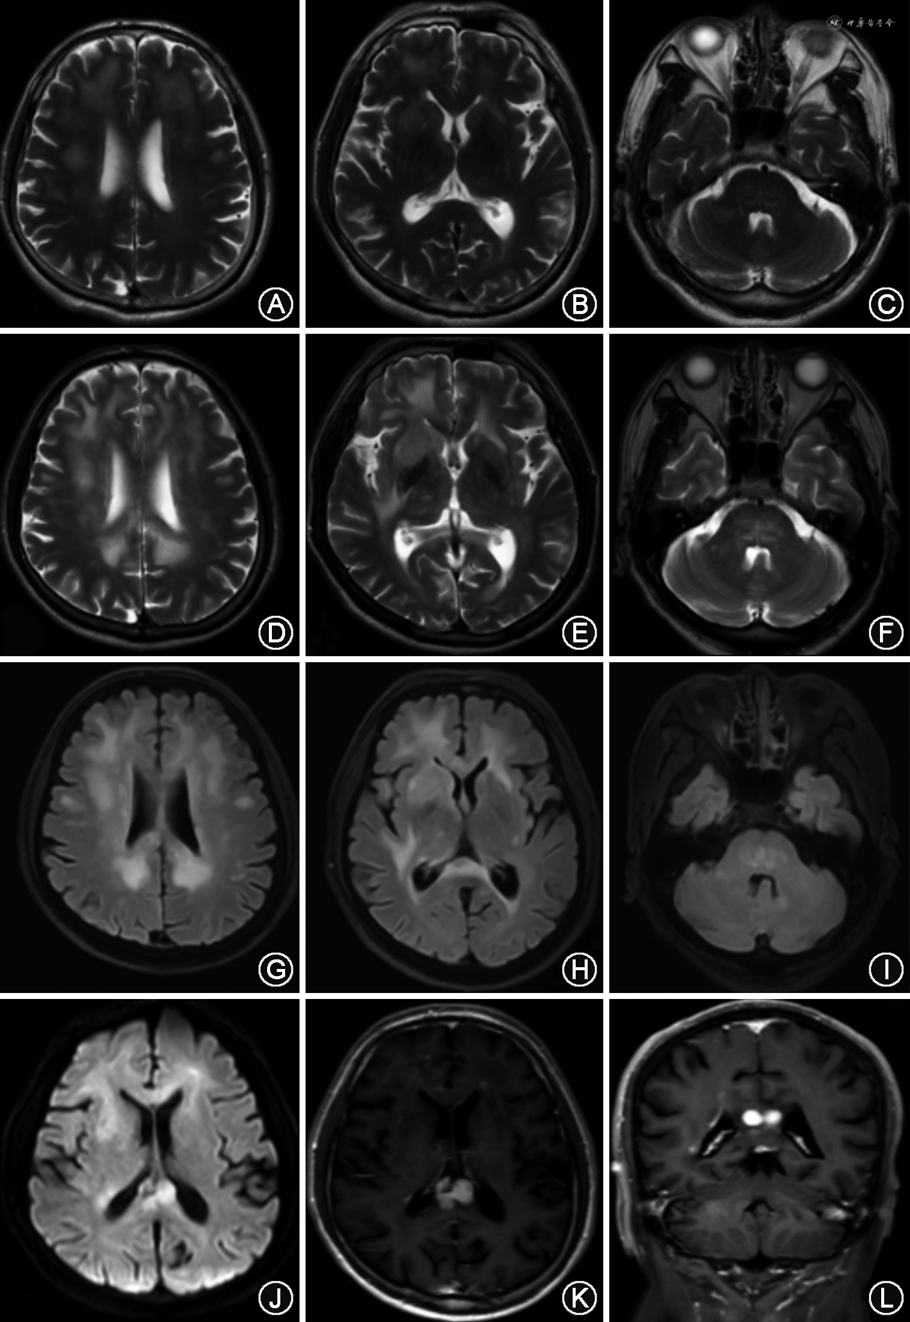

3.头颅影像学特点:病例1的头颅磁共振成像显示双额颞叶白质、脑干、小脑弥漫性病变,局部片状强化。头颅灌注CT提示头CT脑动脉(CTA)及CT脑静脉(CTV)未见明显异常,双侧小脑、双侧额顶枕叶低灌注(图1)。病例2的头颅磁共振成像显示大脑白质多发斑片状病灶,边界不清(图2)。